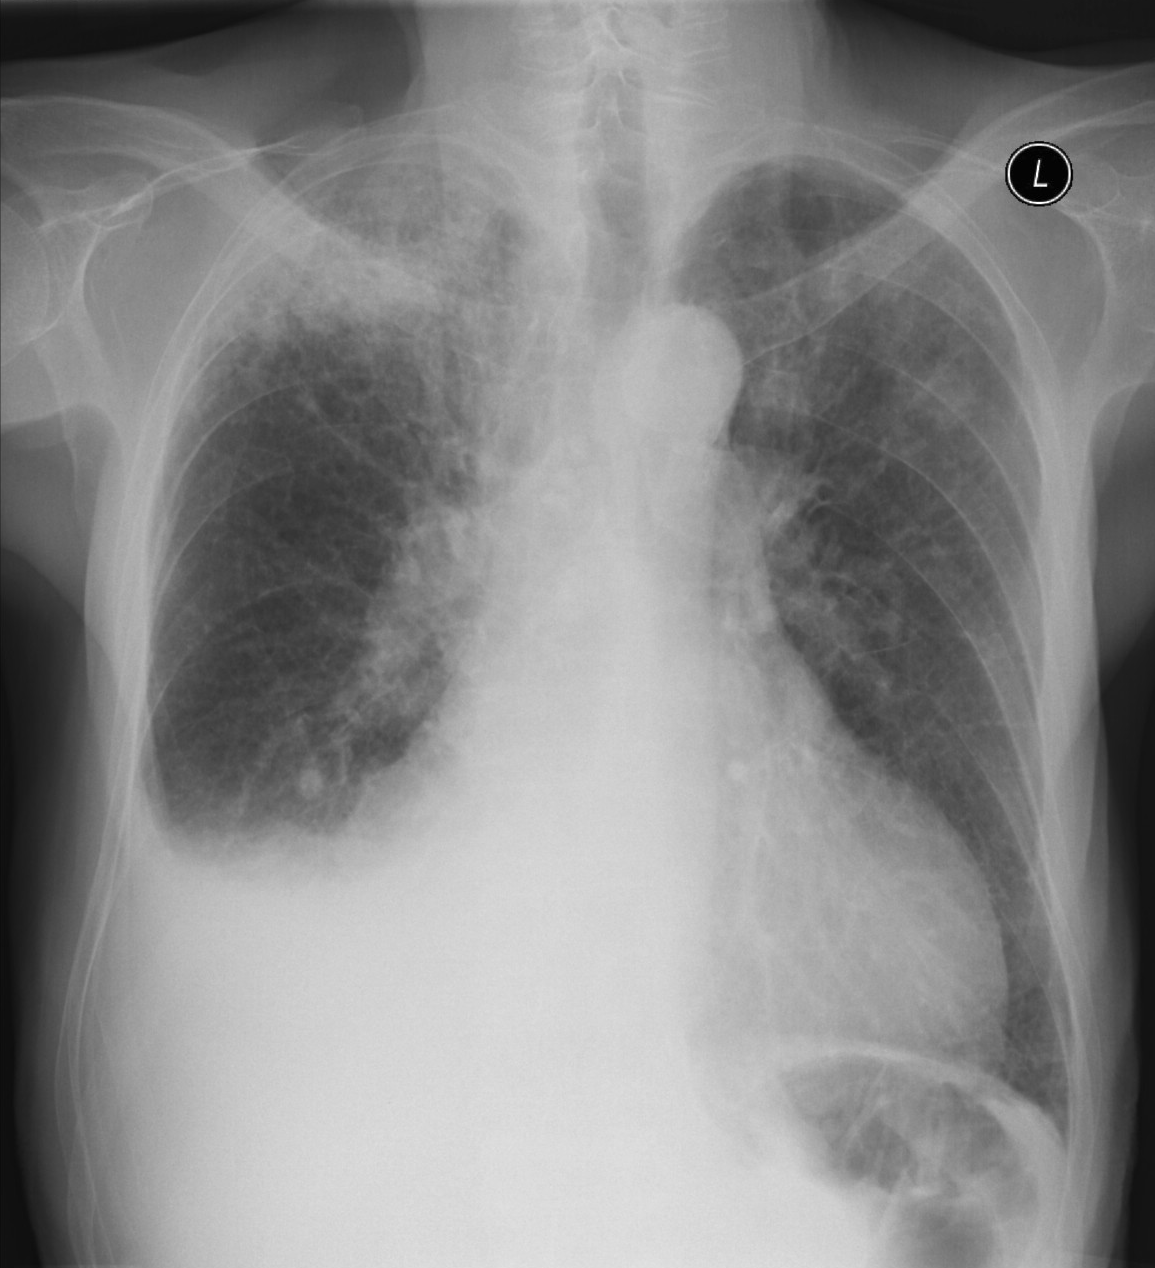

19. Tuberculosis, bidirectional chest radiographs and HRCT. (coronal reconstruction)

75 year old man: hx of hypertension, smoking. Symptoms: dyspnea, productive cough. Moist rales of auscultatory findings above the LLL, tension irritability in the level of lower dorsal spine.

a.) Chest radiograph, bilateral: Mild increased vascular markings. Extensive patchy lobar infiltration in the RUL Previous TB specific lesions in the left apex. The diaphragm contour is blurry on the right side (appr. 4 finger-wide pleural effusion). Cardiomegaly. Medium large dilated sclerotic aorta.

b.) HRCT: Reticular pattern of 10x10x5 cm area in the right apex (1st segment), (septal thickenings), mosaic-like ground glass opacity in the righ apex. Subpleural total atelectasis (mainly 1st segment): irregular mainly nodular soft tissue streak associated with the pleura (max. appr. 1 cm thickness). Some tiny subpleural emphysematous bullae in the right apex.